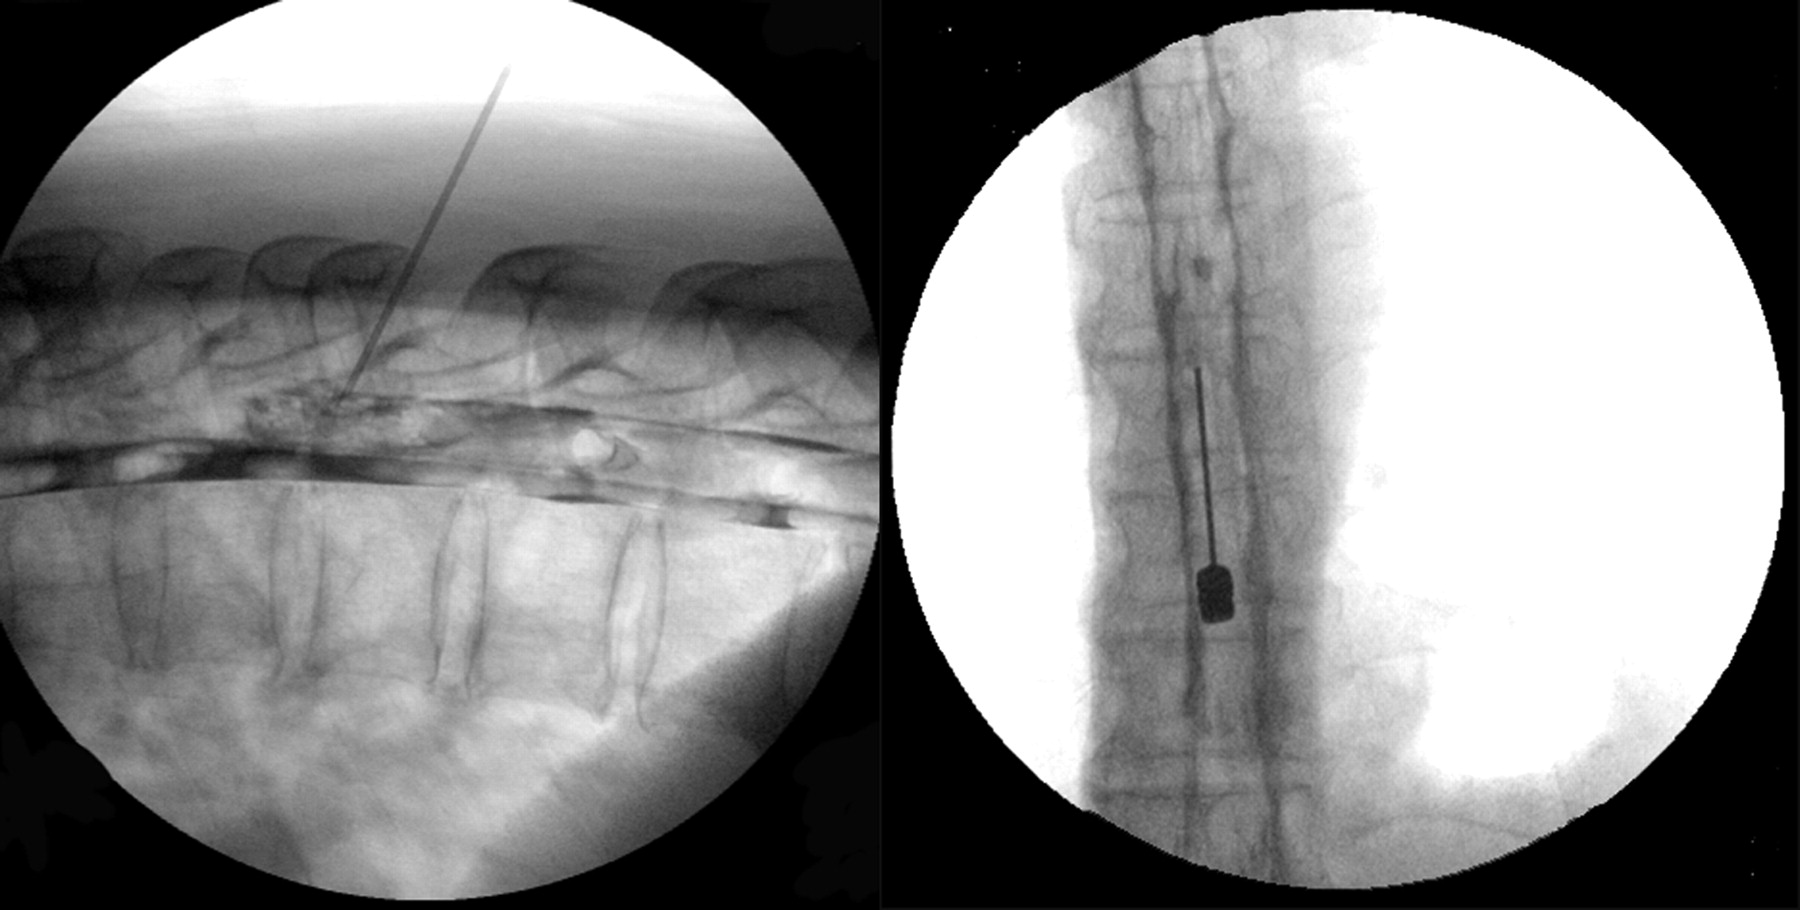

针对EBP也放置使用21-gauge爵针使用相似的技术用于EBP视而不见。硬膜外腔后,在目标位置被确定阻力损失的技术,准确的定位终于透视下经硬膜外腔造影术。此后,荧光镜的指导下在俯卧姿势,10 - 15毫升的自体血混合着对比剂(1 - 2毫升iopamidol)注射,使血液补丁的传播观察(图2)。病人至少保持仰卧的EBP放置后24 - 48小时之内。所有患者接受脊椎CT EBP位置确认后立即修补的分布有针对性的硬膜外腔周围的血液(图3)。没有响应EBP或复发病例在EBP,我们考虑重复EBP。随访时间从6个月到5年不等的意思是4.2年。

技术细节可以提高成功。荧光镜的指导是理想确认针的位置提示硬膜外腔内和硬膜外腔造影术可以确认硬膜外修补区域涵盖了脑脊液漏的位置。此外,9至10毫升的血液的混合物和1毫升的对比剂将直接指导修补血液进入硬膜外腔的分布。最后,脊髓CT扫描后立即获得EBP可以显示分布的修补硬脑膜的囊周围的血液沿着脊柱的长度和是否修补血液适当覆盖硬膜外腔。液体注入血液的一致性在硬膜外的管理也应该被考虑。注入的血液不能沿长轴分布的脊柱由于其粘度。在目前的研究中,脊髓CT扫描后立即执行EBP表明注射自体血与对比剂混合涉及脊柱的各个水平的数量(从5到6到10 - 12水平)从主网站注入。尽管如此,我们建议注射部位应尽可能附近主要的脑脊液漏。